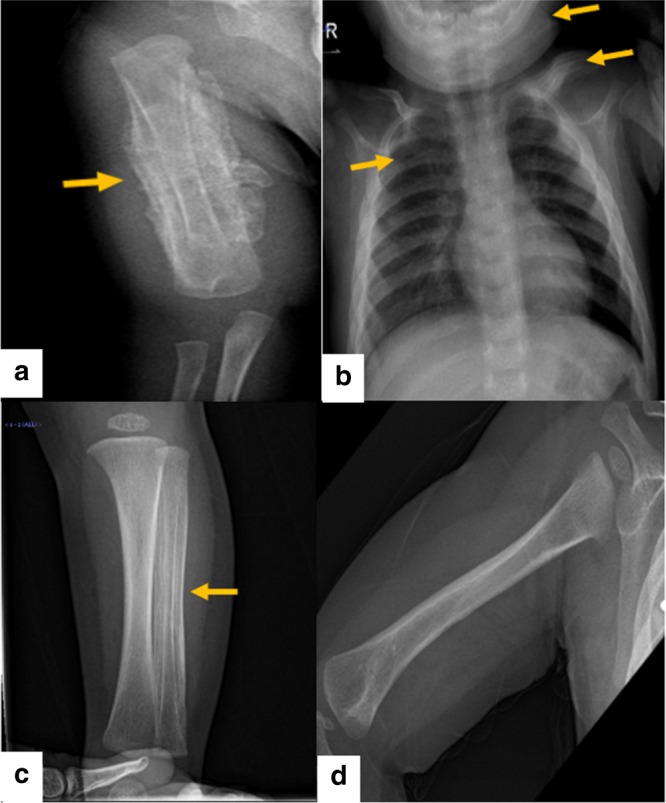

對右臂進行 X 光檢查,顯示沿右肱骨的整個骨干骨膜反應旺盛(圖 1a)。 進一步評估包括 X 線骨骼檢查,顯示一側肩胛骨、一根腓骨、下頜骨和許多肋骨有明顯的骨膜反應(圖 1b)。 根據(jù)臨床和放射學檢查結果,診斷為 ICH。 盡管德托尼-卡菲病可能具有短暫性,但開始使用吲哚美辛(每天 5mg/kg)治療,并且病變在幾個月內(nèi)有效消失,正如后續(xù)放射學檢查所證明的那樣(圖 1c)。 經(jīng)過 1 年的隨訪,患者有效康復,沒有骨骼畸形和/或升高的炎癥標志物。 他仍在服用低劑量的消炎痛(每天 1mg/kg)。

患者的射線照相檢查。 a 沿右肱骨整個軸的骨膜反應。 b 沿左鎖骨、肋骨和下頜骨的骨膜反應。 c 沿腓骨的骨膜反應。 d 肱骨骨膜有效消退